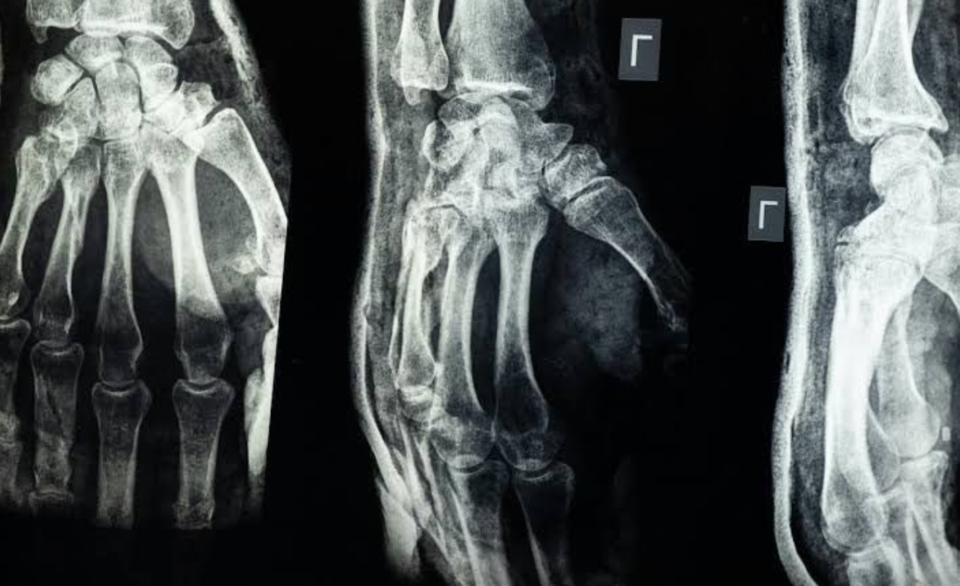

En un laboratorio de la Universidad de Zhejiang, en el este de China, un equipo de científicos acaba de dar un paso que podría cambiar la manera en que se tratan las fracturas óseas. Se trata de Bone 02, un gel adhesivo que promete reparar huesos en apenas tres minutos, sin necesidad de cirugía invasiva ni placas de metal.

Hasta ahora, Bone 02 se probó en más de 150 pacientes con excelentes resultados. El producto une los huesos con gran fuerza y podría reemplazar algunos implantes metálicos, reduciendo además riesgos como infecciones o reacciones adversas.

Los tratamientos tradicionales solo estabilizaban las fracturas sin pegar realmente los huesos. Bone 02, en cambio, combina biología e ingeniería para ofrecer una solución rápida y efectiva, que entusiasma a médicos e investigadores./p12.